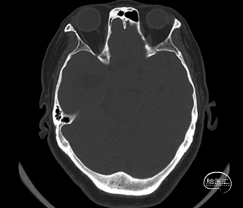

术前影像学资料

术前激素/电解质水平:术前皮质醇、性激素、促肾上腺皮质激素等垂体相关激素,电解质均未见明显异常。

术前诊断:1. 颅咽管瘤 2. 梗阻性脑积水